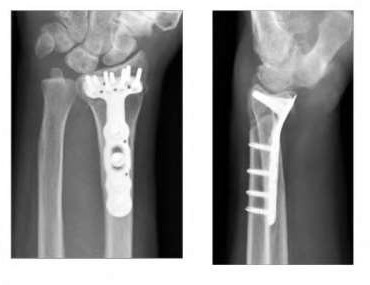

A 35-year-old woman reports wrist pain after a fall onto an outstretched hand. On exam, she has focal tenderness over the wrist snuffbox. A radiograph and CT image are shown in Figures A and B. What is the proper treatment of her injury?